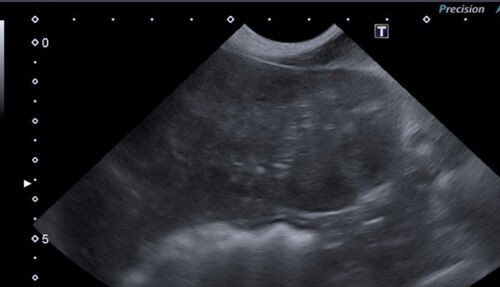

10歳のジャックラッセルテリアの女の子。 もともとの内分泌疾患があり、 定期的に血液検査を行なっていました。 その子に食欲不振が見られたため、腹部の超音波検査を行いました。 そこで、肝臓の左葉に6cm大の腫瘤を確認しました。 さらなる精査のため、CT…

皆様こんにちは。 今回は、健康診断プレミアムコースにて、左の尿管結石が認められた猫ちゃんです。レントゲンでは後腹膜エリアに結石の陰影が確認され、超音波検査では腎臓の腎盂が拡張しており、尿管結石による尿路閉塞で水腎症になっていました。 血液検…